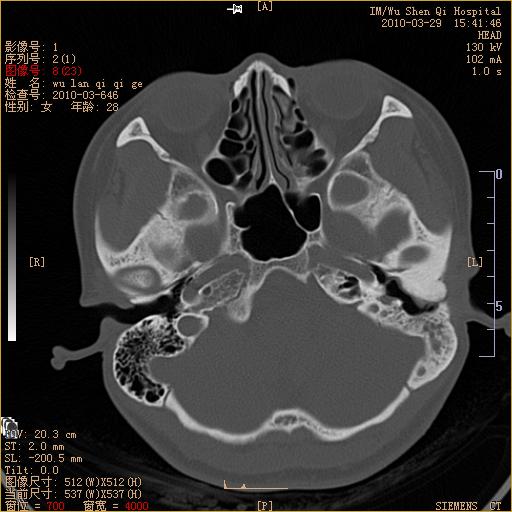

标题: CT25398:女,左耳流脓两年余,带有异物 [打印本页]

标题: CT25398:女,左耳流脓两年余,带有异物

左侧中耳乳突炎,不排除胆脂瘤形成。

左侧中耳乳突炎,胆脂瘤形成。

左侧中耳乳突炎,不排除胆脂瘤形成

1)左侧慢性中耳乳突炎并肉芽肿(或胆脂瘤)形成。2)考虑左侧颞骨慢性炎症伴骨质增生硬化,不排除骨纤。